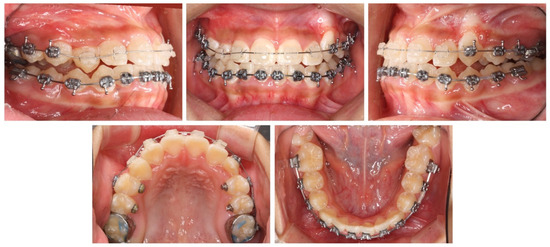

2.4. Treatment Progress